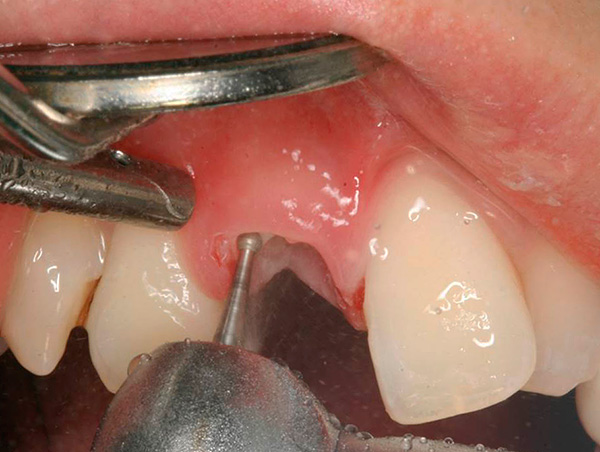

Le fotografie seguenti mostrano l'estrazione del dente, la cui parte della corona viene distrutta quasi al livello delle gengive:

In questi casi, la pinza raramente aiuta a risolvere il problema e un dentista professionista prende ... No, non lo scalpello e il martello. Attualmente, un dentista professionista preferisce approcci moderni per rimuovere tali radici: tagliare con un trapano e rimuovere le radici individualmente con un ascensore e (o) una pinza. Ciò è particolarmente vero per il sesto dente e il dente del giudizio.

Foto di un dente le cui radici sono separate da un trapano prima della rimozione: